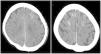

La primera prueba aconsejada, tras una exploración neurológica detallada, generalmente es el TC cerebral sin contraste, en el cual se puede observar edema cerebral y realce cortical de las áreas afectas o del espacio subaracnoideo22, aunque también puede haber ausencia de signos radiológicos20. Especialmente el TC dual energy permite diferenciar si las hiperdensidades observadas corresponden a contraste o hemorragia12. Los casos reportados de pacientes en HD no presentan signos radiológicos distintos (fig. 1). Otra prueba útil es la RM por su capacidad de evidenciar lesiones isquémicas, principalmente con la secuencia DWI mediante la restricción en la difusión producida por la isquemia; la secuencia FLAIR identifica las áreas edematizadas22 (fig. 2). Otro examen que ayuda a la diferenciación, especialmente respecto la hemorragia subaracnoidea, es el análisis del líquido cefalorraquídeo (LCR), donde la ausencia de xantocromía o hematíes iría en contra de esta, así como una concentración de contraste superior a la sanguínea iría de la mano de la extravasación del mismo4.

Resonancia magnética (RM) de mujer de 84 años con hemiplejía izquierda y desviación derecha de la mirada con pérdida de conciencia tras cateterismo cardiaco. RM a las dos horas del procedimiento muestra borramiento de surcos a nivel parieto-occipital derecho respecto a contralateral con hiperintensidad córtico-subcortical a ese nivel en T2 y FLAIR, sugestivo de edema cerebral y ausencia de lesiones isquémicas en DWI. Meng-Ru et al.19 Con permiso de los autores.